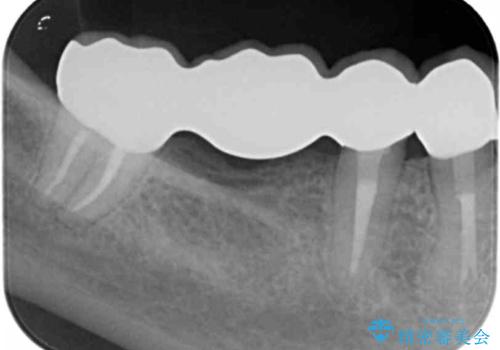

臼歯部メタルフリー再補綴

- 治療してからの年月が経過し、かみにくくなったブリッジ・クラウンを全てやりかえたいと希望され来院されました。

- 110万円(仮歯×8・ファイバーコア×6・ジルコニアクラウン×8)費用は治療当時の料金となります

装着して長期間経過したブリッジやクラウンは隙間から細菌が侵入し虫歯が再発してしまっていることがあります。

長期的に問題のないブリッジ・クラウンを作製するため、虫歯をしっかりと除去すること精密な根管治療を行うことが肝要です。